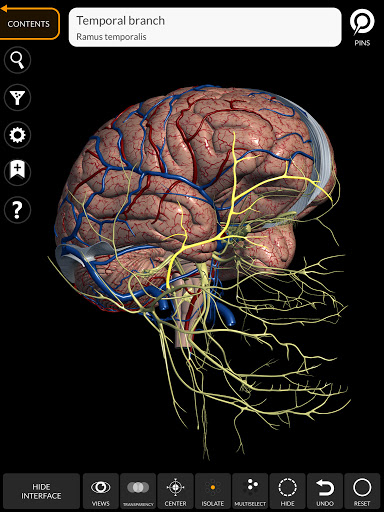

"Anatomy 3D Atlas" memungkinkan Anda mempelajari anatomi manusia dengan cara yang mudah dan interaktif.

Melalui antarmuka yang sederhana dan intuitif, Anda dapat mengamati setiap struktur anatomi dari sudut mana pun.

Model 3D anatomi sangat terperinci dan memiliki tekstur hingga resolusi 4k.

Pembagian berdasarkan wilayah dan tampilan yang telah ditetapkan sebelumnya memudahkan pengamatan dan studi bagian tunggal atau kelompok sistem dan hubungan antara organ yang berbeda.

MODEL ANATOMI 3D

saraf • Sistem pernapasan • Sistem pencernaan • Sistem urogenital (pria dan wanita) • Sistem endokrin • Sistem limfatik • Sistem mata dan telinga FITUR • Antarmuka yang sederhana dan intuitif • Putar dan perbesar setiap model dalam ruang 3D • Opsi untuk menyembunyikan atau mengisolasi satu atau beberapa model yang dipilih • Filter untuk menyembunyikan atau menampilkan setiap sistem • Fungsi pencarian untuk menemukan setiap bagian anatomi dengan mudah • Fungsi penanda untuk menyimpan tampilan khusus • Rotasi cerdas yang menggerakkan pusat rotasi secara otomatis • Fungsi transparansi • Visualisasi otot melalui tingkat lapisan dari yang superfisial hingga yang terdalam • Dengan memilih model atau pin, istilah anatomi terkait akan muncul • Deskripsi otot: asal, • Tampilkan/ Sembunyikan antarmuka UI (sangat berguna dengan layar kecil) MULTIBAHASA • Istilah anatomi dan antarmuka pengguna tersedia dalam 11 bahasa: Latin, Inggris, Prancis, Jerman, Italia, Portugis, Turki, Rusia, Spanyol, Mandarin, Jepang, dan Korea • Istilah anatomi dapat ditampilkan dalam dua bahasa secara bersamaan PERSYARATAN SISTEM • Android 8.0 atau yang lebih baru, perangkat dengan RAM minimal 3GB Reversi